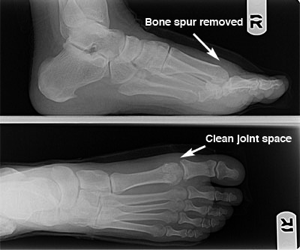

Diagnosis of hallux limitus is made by both physical examination of your foot and by x-ray examination. There is a commonly mild swelling and bony prominence associated with the first metatarso – phalangeal joint behind the big toe.

X-ray examination of the foot will reveal the true severity of the condition. It will allow the physician to evaluate the joint for bone spurs, decrease in joint space, flattening of joint surfaces, and loose bodies in the joint. X-rays can also reveal the causes of hallux limitus such as an elongated or elevated first metatarsal.